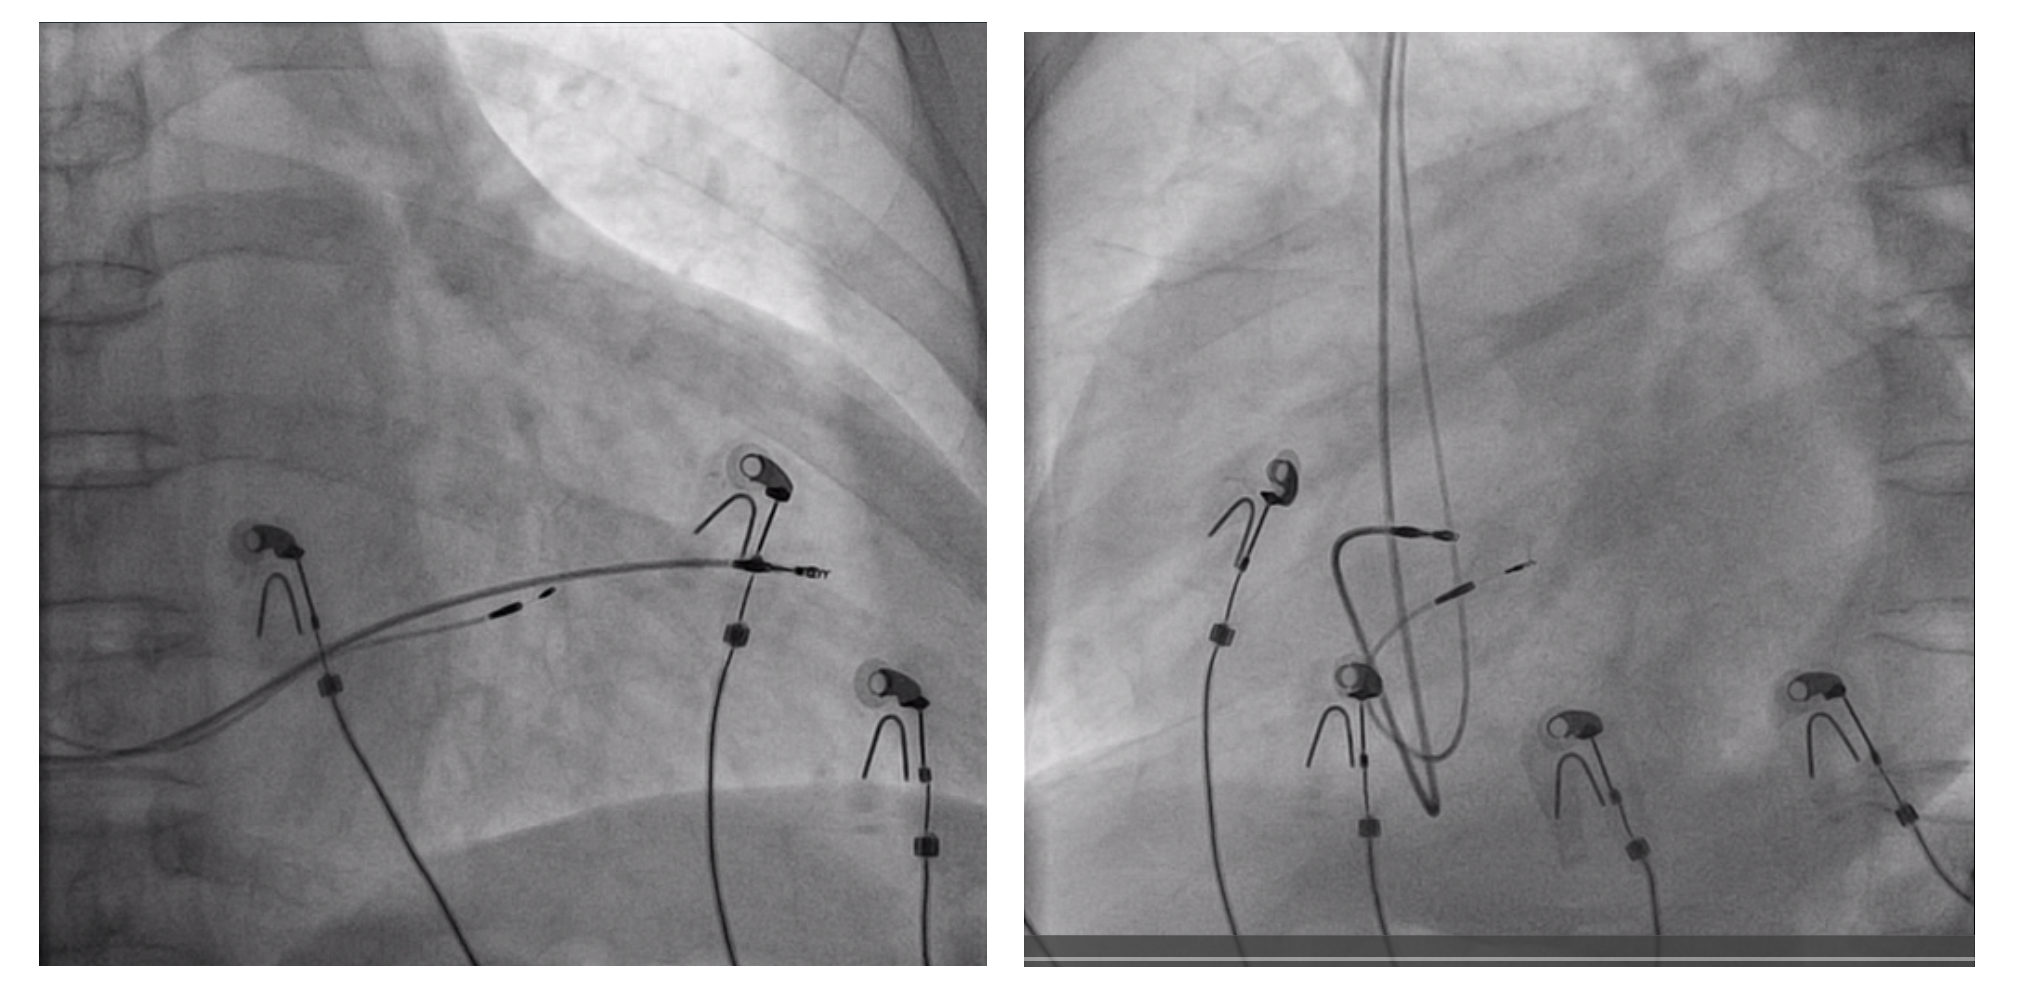

DDD pacemaker with left bundle pacing

crt.png